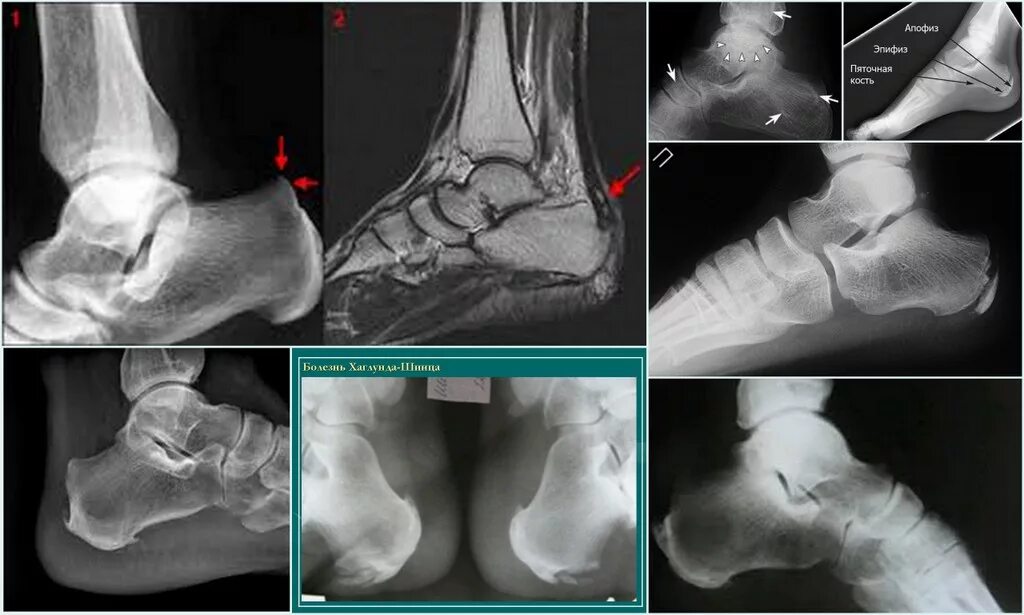

Синдром шпора пяточная